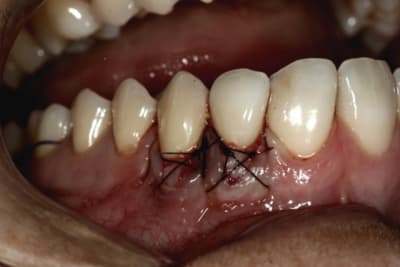

Voilà le résultat à J 0.

Le reste seulement si ça cicatrise bien.

bravo steph ... c'est propre et bien fait ......il semble que tu ais conservé un peu d'épithélium......pourquoi ?

personnellement une petite critique ......j'évite les noeuds en vestibulaire pour limiter le quantité de plaque et faciliter le nettoyage . en plus en nouant à l'intérieur le placage en lingual ou palatin se fait naturellement puisque la traction plaque le fil tout seul .....même parfois trop !

sur ce genre de cas je ne fais plus que des tunellisations et dans ce cas je ne peux garder d'épithélium .....cette technique limite enormement les sutures et je trouve donne de bons résultats.....je ne suis pas sûr que la conservation épithéliale apporte un plus ..et cela rend le travail plus difficile .....mais moi je trouves que tu maitrises tout cela parfaitement.

tu nous montre le résultat quel qu'il soit steph .. moi je suis sur que cela ira .....